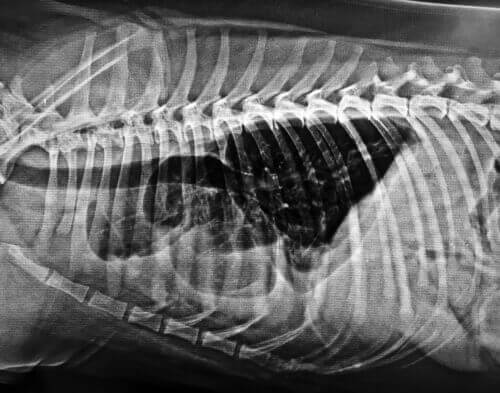

Il coenzima Q10 si utilizza per curare malattie cardiache come l’insufficienza cardiaca congestizia che produce un accumulo di liquidi nel corpo.

Vari studi hanno dimostrato che nel cuore degli animali domestici con malattie cardiache i livelli di CoQ10 si abbassano. Di conseguenza, si usa questo coenzima come coadiuvante nel trattamento dell’insufficienza cardiaca congestizia.

Il coenzima Q10 è efficace nel trattamento della cardiomiopatia canina e delle malattie correlate.